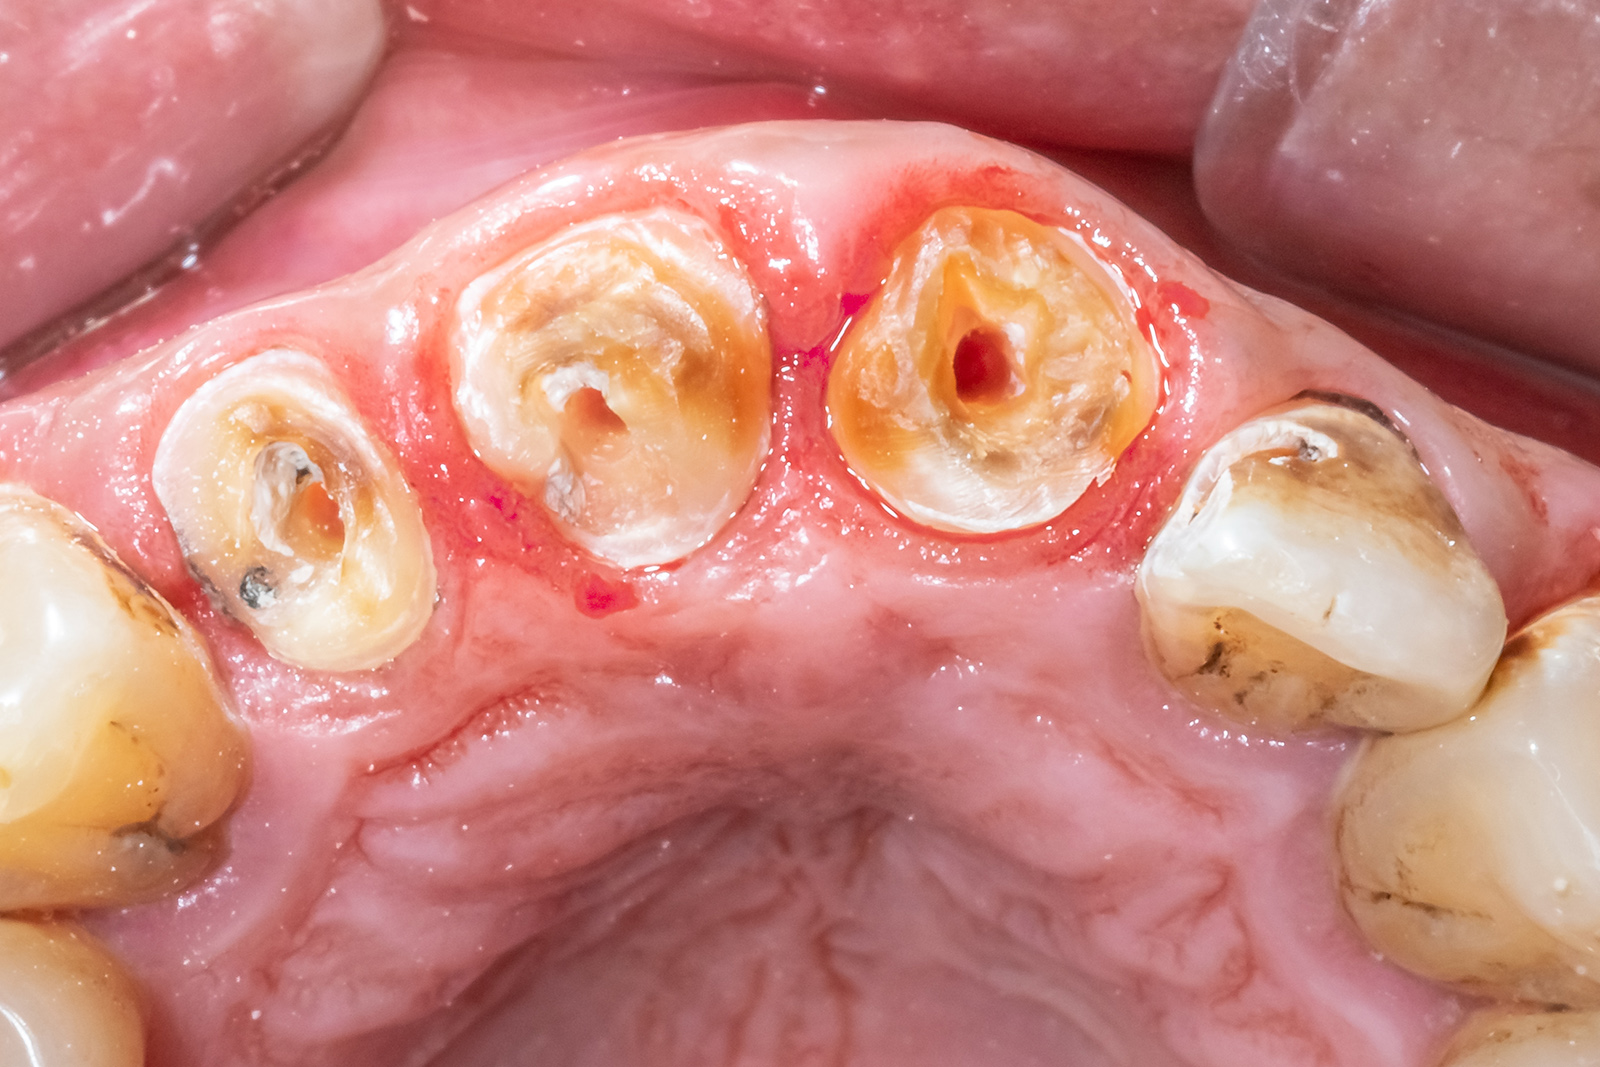

重度の虫歯治療「エクストリュージョン法」

虫歯が進行し、崩壊してしまった歯は多くの場合、抜歯が必要と診断されます。

通常の虫歯治療では、損傷した部分を削り、被せ物を装着します。しかし、重度に崩壊した場合、被せ物を取り付けるための場所がなくなってしまいます。

そんな中で、エクストリュージョン法という方法があります。この方法は、抜歯をせずに治療できる選択肢の一つです。エクストリュージョン法は矯正治療の一種であり、残された歯の根を歯茎の外側に引き出すことで、被せ物を取り付けるための土台を作ります。

クラウンレングスニング

重度の虫歯でも歯を残す治療法として、先に紹介した「エクストリュージョン」と同様、当院では「クラウンレングスニング」という治療も行っています。

クラウンレングスニングは、歯ぐきをわずかに切開して、歯の根の一部を露出させる治療です。

こうすることで、被せ物をしっかり固定できるだけの歯の高さを確保します。